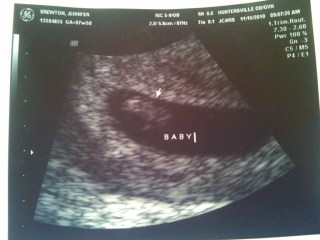

After 2 painfully long weeks of waiting, we had our second ultrasound appointment to make sure we were progressing as we should be. The appointment was on November 15th, Dan’s birthday, and we was at the appointment with me so he was able to calm my nerves a little bit before hand, but seeing and hearing the baby’s heartbeat was what really did it for me! We could see our tiny little baby and the even tinier flicker of it’s heart beating and it was the best thing in the world! The ultrasound tech clarified that we were in fact right on target with our estimated due date, (not like the last appointment where I was measureing small) and the baby was measuring just over 7 weeks. All babies grow at different paces, so we were relieved at the news and I was able to let myself get a little more excited! Below is a photo, a little dark and kind of hard to decipher, but that little whitish blob looking thing is the baby : )

2nd Ultrasound